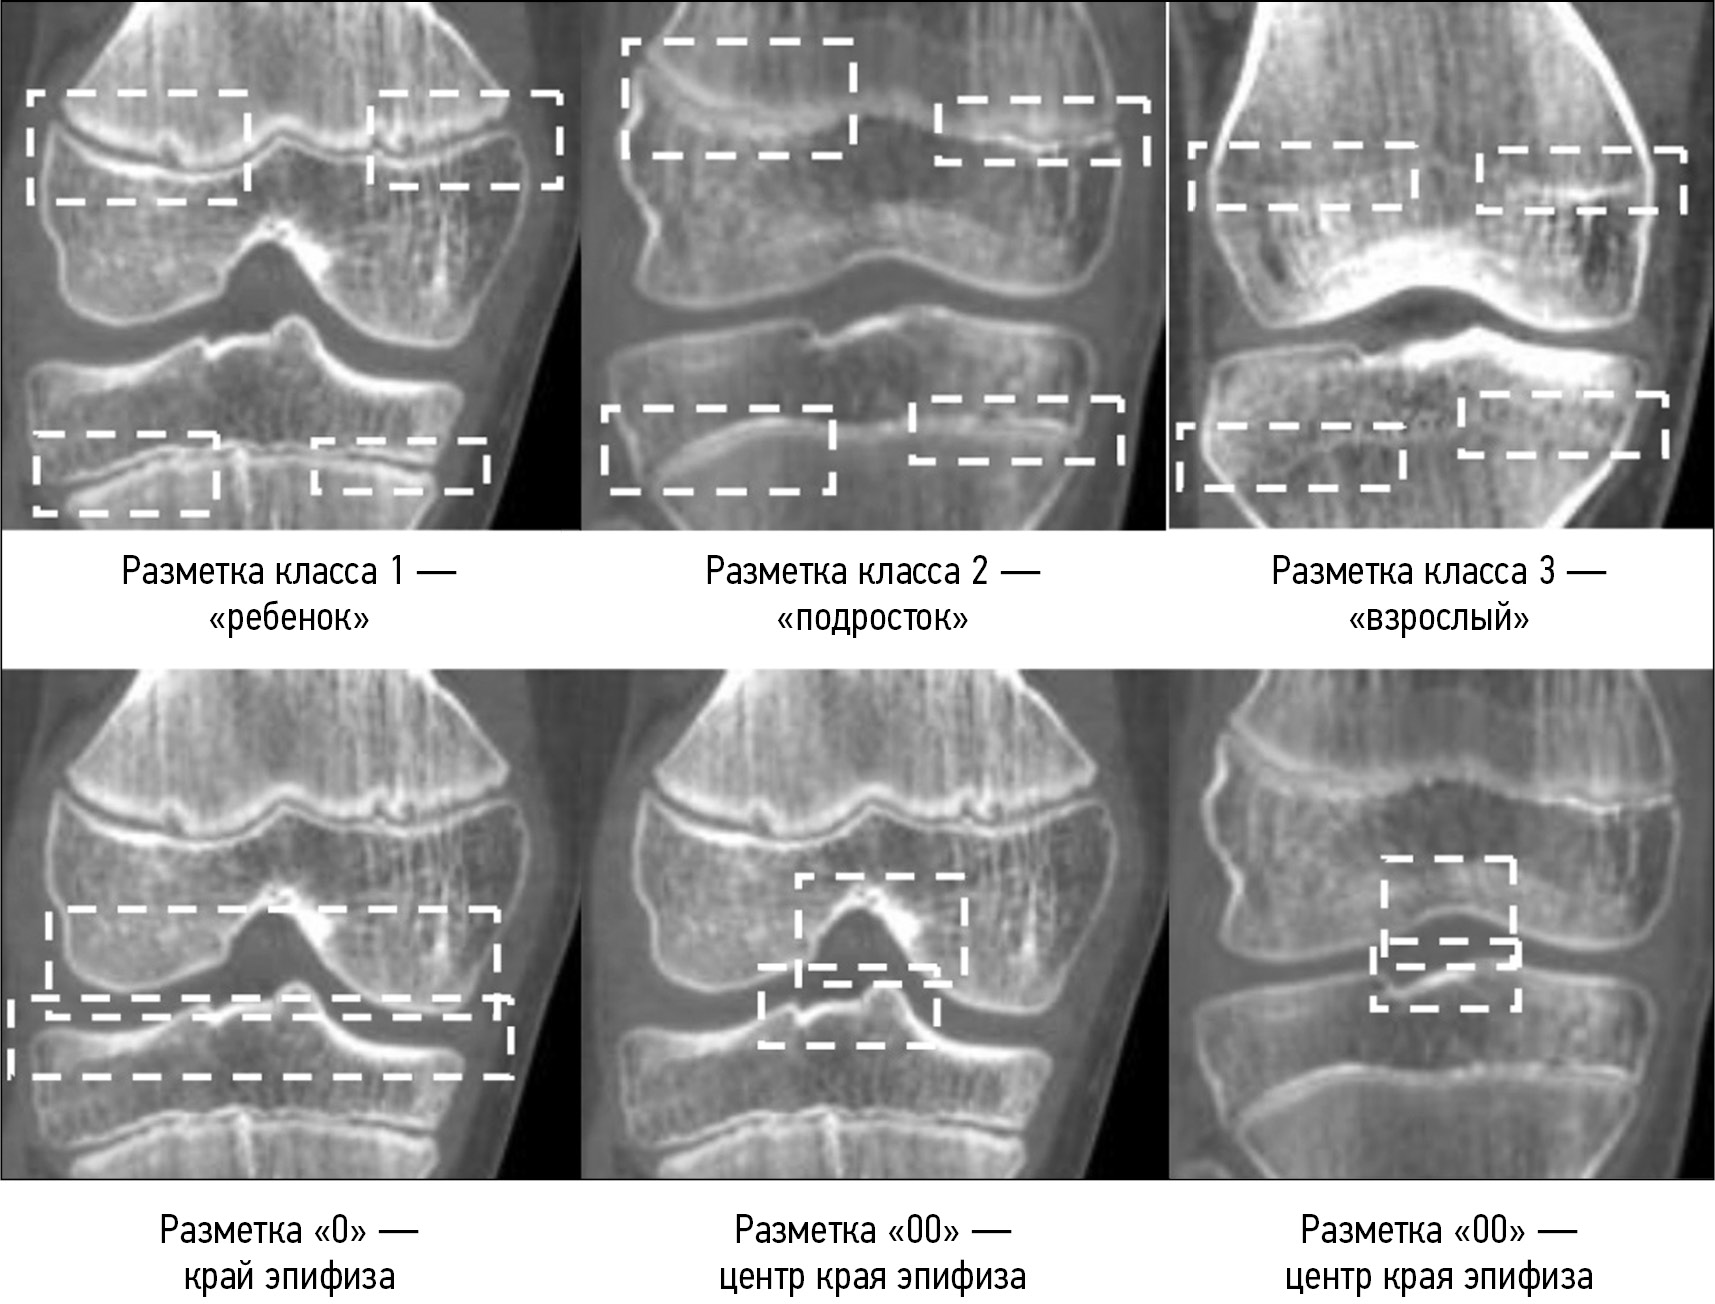

Доступный набор КТ-снимков был разделён на обучающий (70%), тестовый (16%) и проверочный (14%). Первоначально производилось обучение нейронной сети для выделения областей интереса и предварительной классификации, т.е. отнесения индивидуума к одной из трёх возрастных групп. В качестве исходных данных использовались изображения КТ коленного сустава в сагиттальной проекции, которые были обработаны (сегментированы) с использованием программного обеспечения InVesalius 3.1.1 и экспортированы в виде файлов JPEG. Полученные в результате преобразования серии снимков размечались вручную (https://www.makesense.ai/). Размечалось каждое изображение. Вначале размечались области края эпифиза («0») и центра эпифиза («00»). Затем производилась разметка классов отдельно для центральной части эпифиза и периферии. Принцип наименования классов следующий:

- класс 1 ― эпифиз и метафиз полностью разъединены, эпифизарная линия визуально определяется как двойная (класс, условно обозначенный как «ребёнок»);

- класс 2 ― начальный этап сращения: наличие участков сращения в центре в виде одинарной линии и двойной по периферии («подросток»);

- класс 3 ― полностью сросшаяся, оссифицированная эпифизарная линия («взрослый»).

Примеры разметки эталонных классов представлены на рис. 1.

Рис. 1. Разметка объектов на изображении, применяемая при реализации метода.

Fig. 1. Marking of objects in the image used in the implementation of the method.